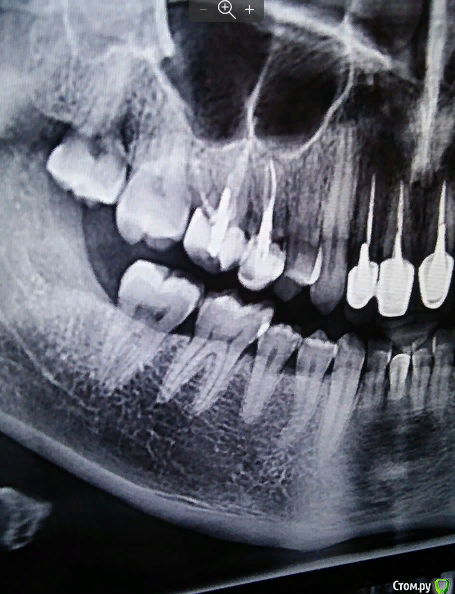

kryger2010 Опубликовано 10 сентября, 2019 Автор Поделиться Опубликовано 10 сентября, 2019 Вечером выложу рентген но он прицельный, есть панорамный снимок, но сделанный до установки коронки... Ссылка на комментарий

kryger2010 Опубликовано 10 сентября, 2019 Автор Поделиться Опубликовано 10 сентября, 2019 До установки и после Ссылка на комментарий

DmitrySH Опубликовано 11 сентября, 2019 Поделиться Опубликовано 11 сентября, 2019 Здравствуйте. По вашим снимкам сложно сказать что-то конкретное. Прицельный снимок сделан так, что прилегание коронки по нему невозможно оценить. Но видно у зуба 15 есть хроническое воспаление и пародонтальный карман. 2 Ссылка на комментарий

St. Опубликовано 11 сентября, 2019 Поделиться Опубликовано 11 сентября, 2019 Посмотрите пожалуйста присоединяюсь к ответу выше. Снимок с коронкой сделан слегка под углом и по нему не понятно как коронка соотносится с корнем. воспалена десна, а я ее еще и руками трогаю периодически и тем самым провоцирую "замкнутый круг" болит, ищу причину и трогаю и тем самым усугубляю все. вполне логичное обьяснение. В таком случае чистить как обычно(только щетку лучше все же средней жесткости), плюс мазать десну метрогилом, полоскать хлоргексидином 0,05%, и пока на неделю-другую оставить в покое.Понаблюдайте поменяется ли что-то. он появился из за нависающей пломбы,......карман как понимаю, полному устранению не подлежит. Да 1 Ссылка на комментарий